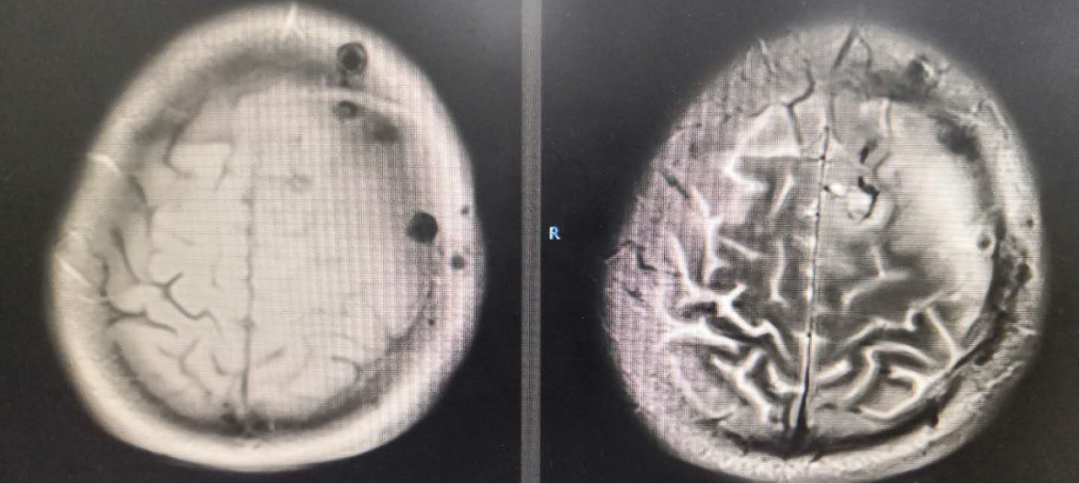

放疗范围

术后放疗处方剂量:PTV1:59.92Gy/2.14Gy/28F,PTV2:50.40Gy /1.80Gy/28F。

虽然病理报告提示是二级,考虑到颅脑功能区手术欠彻底,按高级别胶质瘤,放疗同步口服“替莫唑胺”化疗。